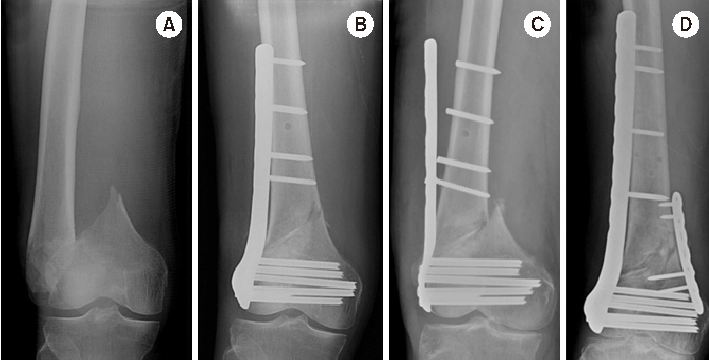

Fig. 2

Direct reduction methods in the coronal plane in distal femur fractures using a long hemostatic tonsil (A), Collinear reduction clamp (B), percutaneous wiring (C), or conventional cortical screw (D).